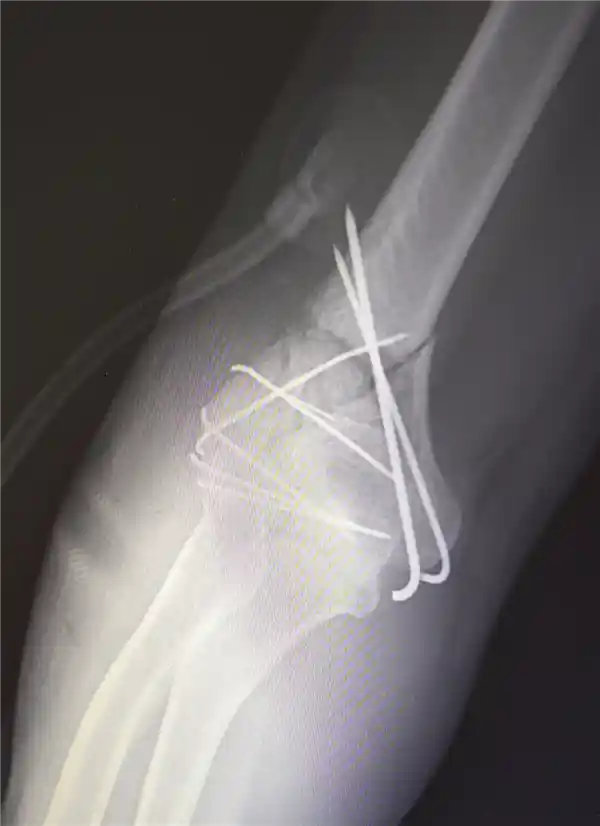

由于男子多处骨折,其中最严重的是右肘部C3型粉碎性骨折,关节面及髁上部位严重碎裂(碎成七块),肘关节容易发生粘连,复位和固定手术难度非常大。

最终医疗团队运用了类似修复古董瓷器的“拼古董”复位固定技术,先将大块骨片进行拼接,再处理小块碎片,先后实施了两次手术。

部分手术后拍摄的影像